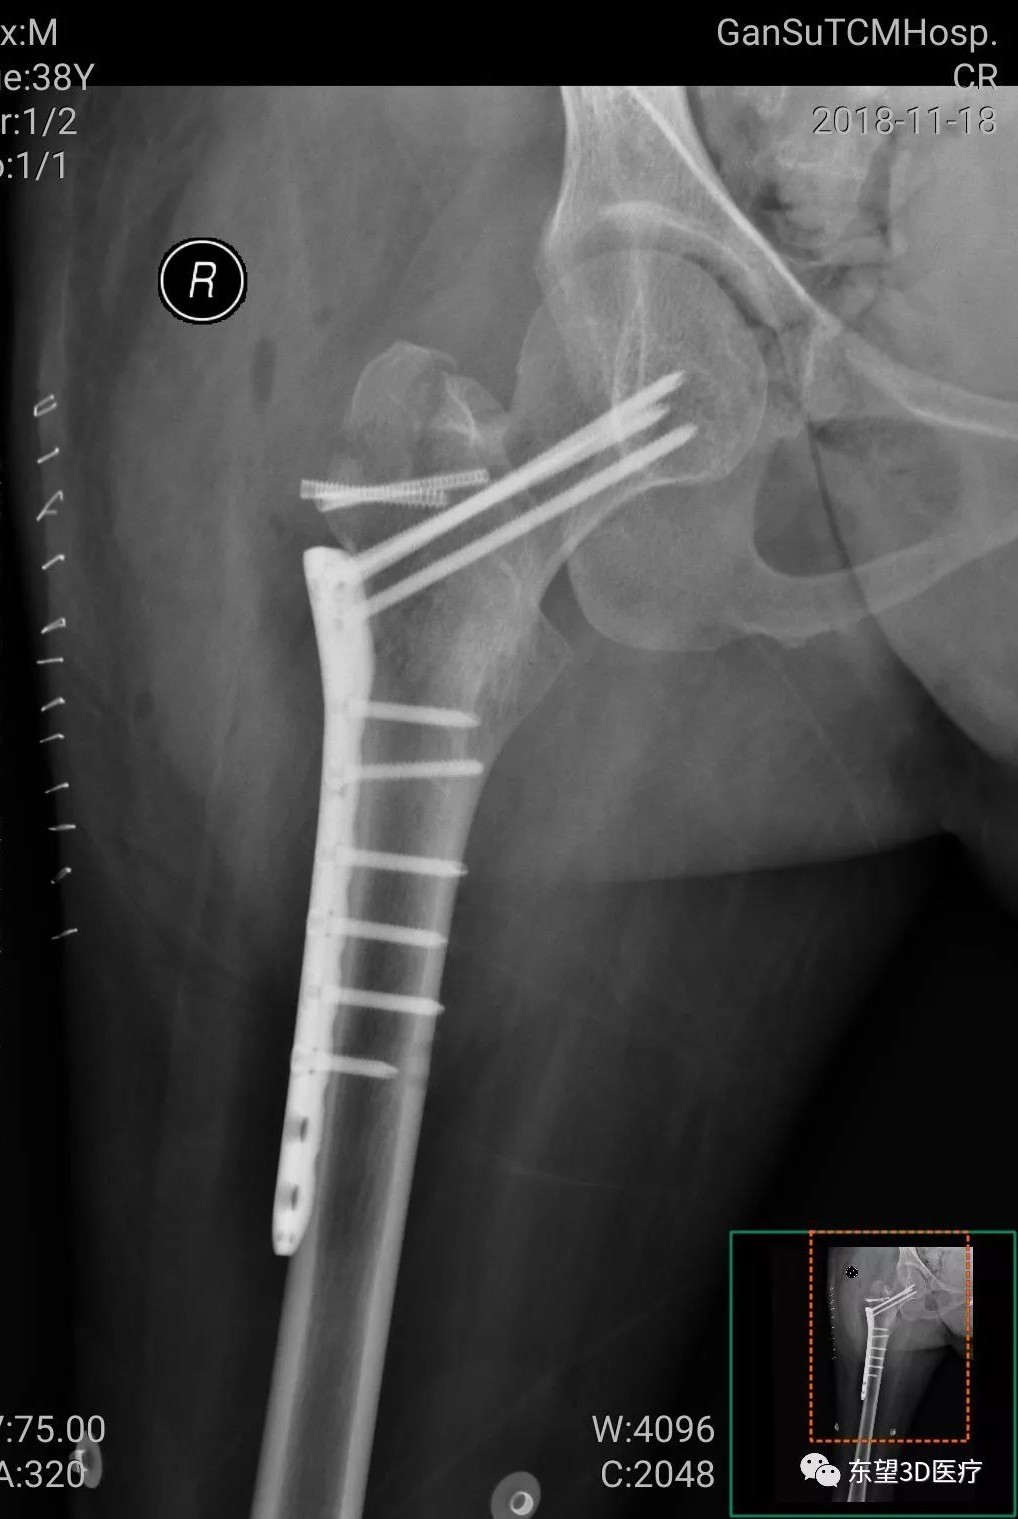

患者男 38歲

診斷:右股骨粗隆間骨折

手術方案:切開復位內固定術

輔助工具:3D打印病理模型

術前影像數據

3D打印成型,1:1還原骨折部位各個骨塊的位置關系